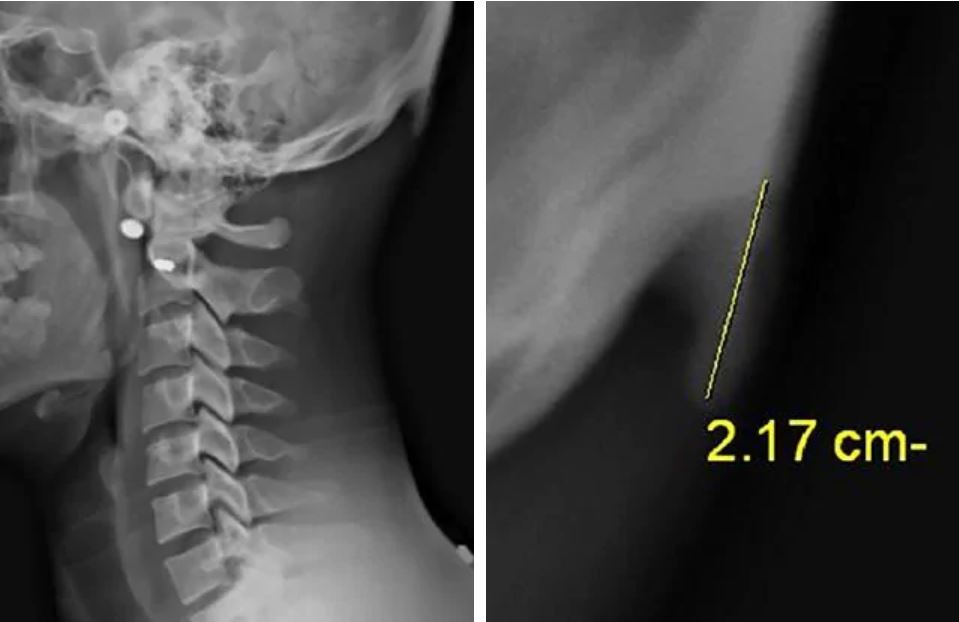

Dos investigadores australianos hicieron el extraño descubrimiento mientras examinaban cientos de radiografías de personas entre 18 y 30 años, observando que casi la mitad había desarrollado crecimientos óseos que normalmente se pueden ver en personas ancianas que han mantenido una mala postura a lo largo del tiempo, generalmente encorvada.

El estudio sostiene que se están formando estos cuernos en base al análisis que de 218 radiografías de personas de 18 a 30 años de edad. Determinaron que de ellas el 41% había desarrollado un bulto óseo de 10 a 30 milímetros en la parte posterior de su cráneo.

"Es importante comprender que, en la mayoría de los casos, los espolones óseos miden unos pocos milímetros individuales y, sin embargo, encontramos proyecciones de 10 a 30 milímetros en la población joven estudiada", comentó el investigador.